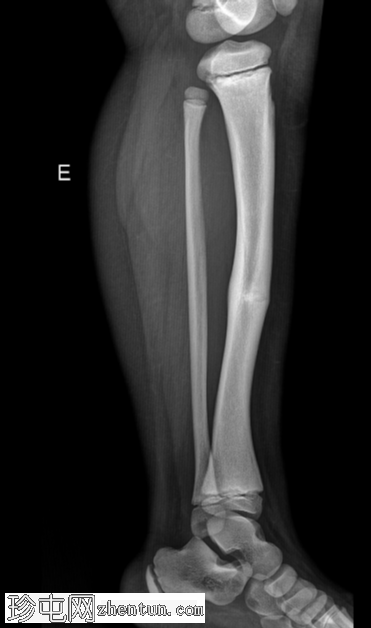

右大腿隐痛持续数日。已知有致密性骨发育不良病史。

年龄:10岁

性别:男

X光片

侧面

弥漫性骨密度增高。

长骨髓质变窄。

右股骨不完全性骨折,骨折后功能不全。

双侧胫骨骨干先前骨折后出现骨重塑。